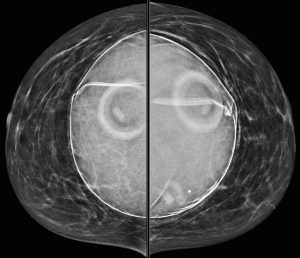

A 46-year-old woman presents with a tender and palpable left breast abnormality. A diagnostic mammogram is performed:

Explanation: These implants are filled with saline. Note the “see through” density of the saline, compared to the extremely dense silicone implant that was demonstrated in a previous case. We can also see the implant valves and mild rippling of the external implant contour, which are features typically associated with saline implants.

On the MLO images, we can see the pectoralis major wrapping around the anterior portion of the implant, which indicates that they are retropectoral implants (also known as “subpectoral”).